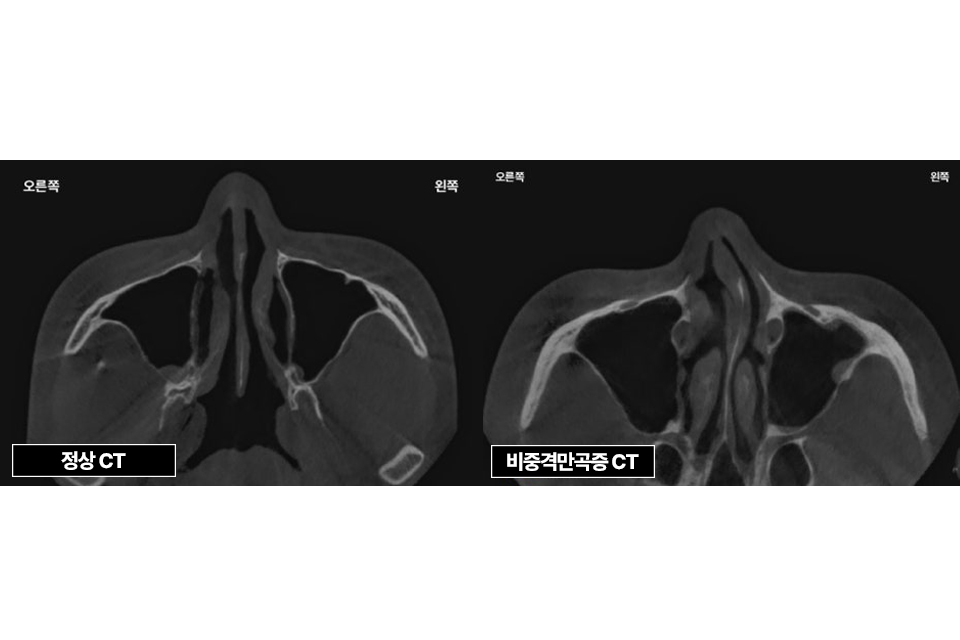

삼성드림이비인후과의 누적된 데이터로 비중격만곡증을 분석합니다.